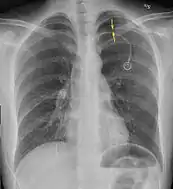

Chest X-ray

A plain chest radiograph, ideally with the X-ray beams being projected from the back (posteroanterior, or "PA"), and during maximal inspiration (holding one's breath), is the most appropriate first investigation.[30] It is not believed that routinely taking images during expiration would confer any benefit.[31] Still, they may be useful in the detection of a pneumothorax when clinical suspicion is high but yet an inspiratory radiograph appears normal.[32] Also, if the PA X-ray does not show a pneumothorax but there is a strong suspicion of one, lateral X-rays (with beams projecting from the side) may be performed, but this is not routine practice.[15][19]

Anteroposterior inspired X-ray, showing subtle left-sided pneumothorax caused by port insertion

Anteroposterior expired X-ray at the same time, more clearly showing the pneumothorax in this case